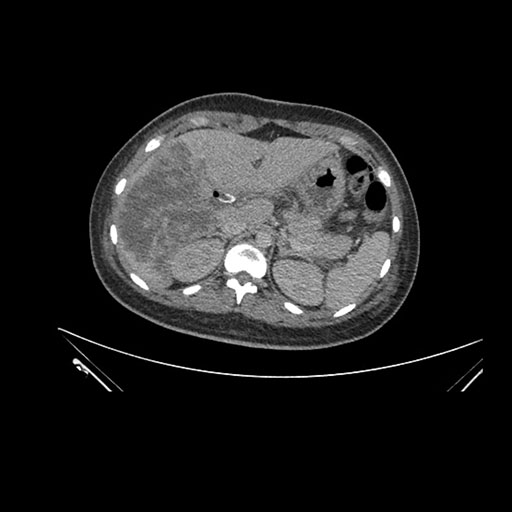

Axial Venous